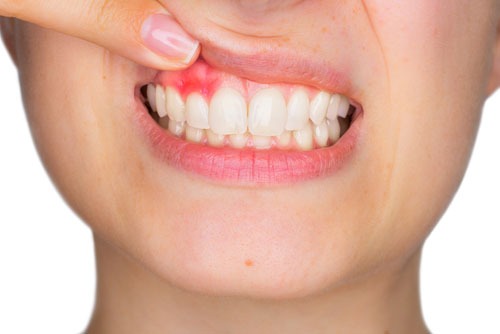

歯周膿瘍とは歯肉が腫れ・膿(うみ)が出てくる病気です。

歯肉がプクッと赤く腫れて膿が出たり、歯を磨いているときでなくても歯ぐきから出血するという状態です。また、多くの場合、口臭も出ます。